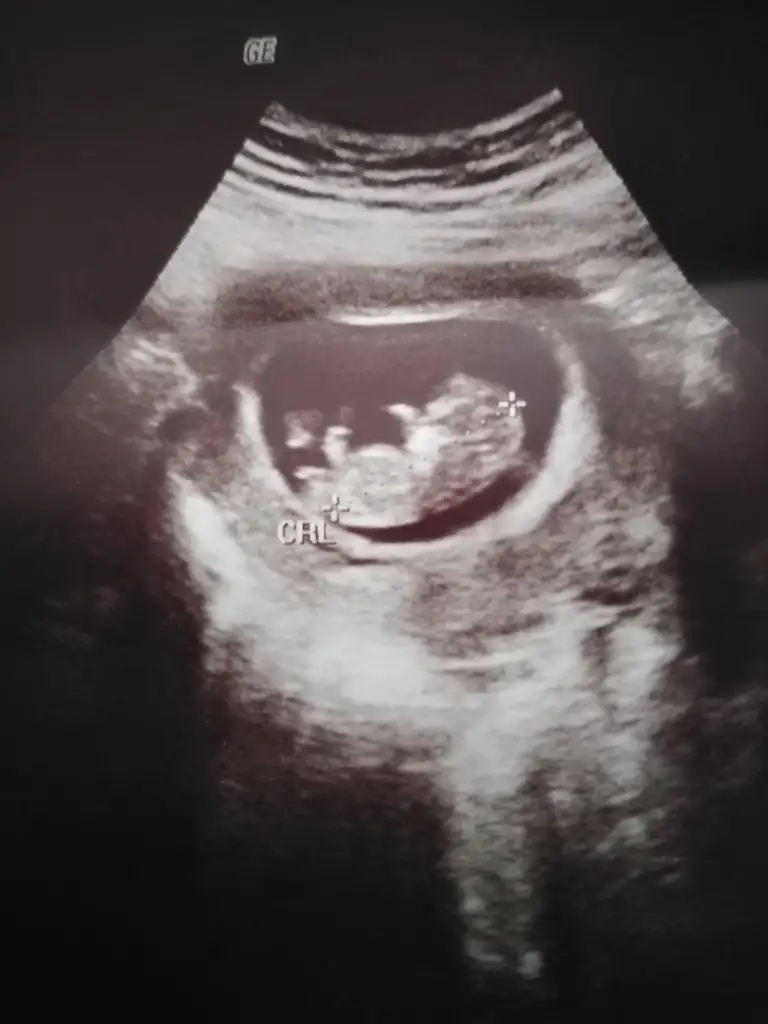

İlk ultrason resimlerinizi paylaşın ramzi teorisine göre cinsiyeti tahmin edeyim bakalım tutacak mı?

İlk iki resim ilk ultrason sonrakiler de en son ultrason bende tahmin alabilirmiyim

Arkadaşlar bugün karından ultrason çekildi, 6+3 , bir oğlum var ,bir de kızım olsun çok istiyorum:) bana da yorum yaparsanız çok sevinirim, heyecanla bekliyorum